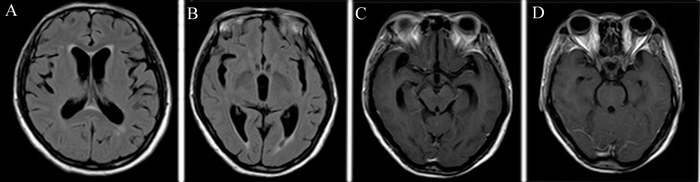

头颅MRI+增强扫描+磁共振血管成像(MRA)示:① 右侧额顶叶局部脑沟液体衰减反转恢复(FLAIR)序列信号稍显模糊,增强后呈线样强化影,需排除脑膜炎可能;② 脑白质多发变性灶;③ 弥漫性轻度脑萎缩;④ 半球MRA示脑动脉硬化(轻度)、右侧胚胎型大脑后动脉及右侧大脑前动脉A1段细小。胸部CT平扫+增强示:① 考虑右肺下叶背段周围型肺癌;② 纵隔淋巴结肿大,考虑为癌转移;③ 胸骨、脊柱多发转移灶;④ 心包积液;⑤ 双肺下叶少许坠积性炎症。行全身正电子发射计算机断层显像(PET-CT)示:① 右肺下叶后基底段致密结节灶,糖代谢增高,考虑周围性肺癌;纵膈多发淋巴结影,糖代谢增高,考虑为癌转移;② 双肺多发小结节灶,糖代谢未见增高,考虑转移瘤;③ 枕骨斜坡、双侧肱骨、双侧肩胛骨、双侧锁骨、胸骨、双侧多根肋骨、脊柱多个椎体及附件、骨盆诸骨、双侧股骨上段多发混合型骨质破坏,部分糖代谢增高,考虑转移瘤;④ 左侧肾上腺增粗,糖代谢增高,考虑转移瘤可能;⑤ 脑萎缩,胸部未见糖代谢异常增高灶,需结合MRI检查综合评估;⑥ 心包积液;⑦ 未见氟代脱氧葡萄糖代谢异常增高灶。

图 3 该例脑膜转移癌患者头颅MRI+增强扫描

脑膜转移癌又称脑膜癌病或癌性脑膜炎,是恶性肿瘤细胞通过脑脊液循环播散到软脑膜、脊膜、蛛网膜和蛛网膜下隙导致神经系统功能障碍的一类疾病,其预后较差,据统计,脑膜转移癌患者平均中位生存期为2.3个月,经积极治疗的脑膜转移癌患者中位生存期也仅为150 d[4]。脑膜转移癌患者癌细胞通常沿着脑膜弥漫性浸润,累及大脑半球、颅神经、软脑膜,临床以头痛、呕吐等颅内高压的表现最常见,其他颅神经受累以复视、视力下降、面部麻木、听力下降、眩晕多见,脊髓神经根受累可出现颈背部疼痛,双下肢无力、麻痹等,也可出现脑病样表现、癫痫发作等[5]。癌细胞累及软脑膜、蛛网膜,导致脑脊液循环不畅,约一半患者会出现交通性脑积水[6]。本例患者MRI表现为侧脑室颞角、侧裂池扩大,第三脑室扩张,呈脑萎缩样的影像学改变,被误诊为脑萎缩。MRI增强扫描对本病的诊断有一定作用,增强扫描后可见脑膜强化,但这些表现并无特异性,只要存在颅内高压或颅内炎症均可有以上表现,往往易被误诊为脑膜炎。